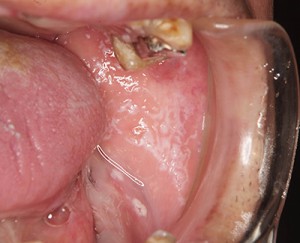

一般的は口腔カンジダ症という病気が多いです。

まさにカビの一種である真菌という菌による感染症です。この菌は元々お口のなかに存在している菌であり、健康な人であればカンジダ症が発症することはあまりありません。

症状としては頬粘膜に白い斑状の膜ができているのが確認できます。

カンジダ症の場合はガーゼで白斑を拭き取ることができるので、他の白斑を生じる病気と区別することができます。